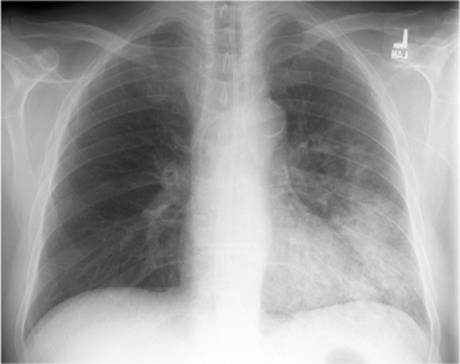

Homogeneous airspace disease confined to a single lobe with an irregular margin (Fig. 5.16) is the most common radiographic pattern, seen in about one-third of patients. Pneumococcal pneumonia is one of the causes of expansive consolidation with bowing of fissures. More widespread patchy bronchopneumonia is seen in another one-third, usually confined to a single lobe. Interstitial opacification simulating viral or atypical pneumonia occurs in one-fourth of patients. The remainder show a mixed patchy and interstitial pattern. There is a predilection for the lower lobes. Pleural effusions are seen in one-third. Consolidation in pneumococcal pneumonia is said to clear by central “lysis.” Patients with shorter clinical histories tend to show more rapid radiographic resolution. As in all pneumonias there is a lag period between clinical resolution and radiologic resolution, which can be several weeks.